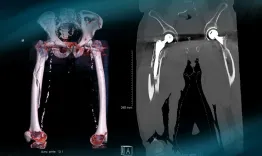

A 71-year-old male, who underwent a right Total Hip Arthroplasty (THA) 12 years ago and a left THA 5 years ago for hip osteoarthritis, recently experienced a fall while walking.

Management of a peri prostetic femoral fracture